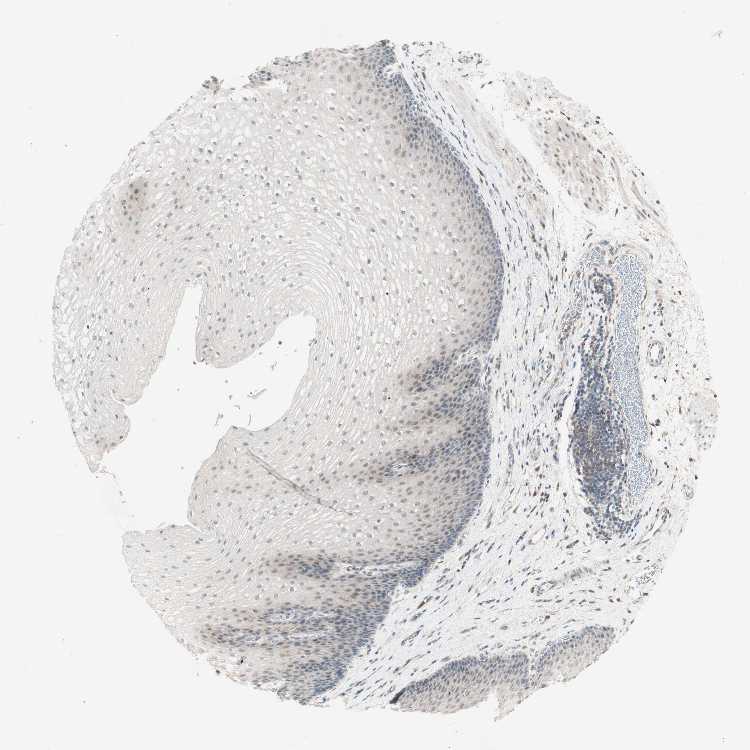

ESOPHAGUS - Antibody stainingi

Antibody staining in the annotated cell types in the current human tissue is reported as not detected, low, medium, or high, based on conventional immunohistochemistry profiling in selected tissues. This score is based on the combination of the staining intensity and fraction of stained cells.

Each image is clickable and will lead to virtual microscopy that enables deeper exploration of all samples and also displays staining intensity scores, fraction scores and subcellular localization as well as patient and tissue information for each sample.

Antibody HPA011070

Squamous epithelial cells Not detected